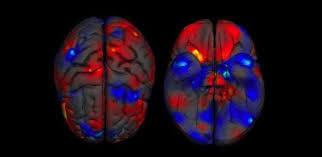

-الاتصال بين أجزأء دماغ الرجل يتم من الأمام إلى الخلف، أما الترابط في دماغ المرأة فيتم من الجانبين، بين اليمين واليسارهو مبين في الشكل 1

-اثبت البروفيسور لاري كاهيل، وهو أستاذ مشارك في علم الاعصاب والسلوك،أن دماغ الرجل يعالج المعلومات بطريقة تختلف عن دماغ المرأة واستخدم جهاز position emission tomography ;وأظهرت الصور أن المناطق التي تنشط في دماغ المرأة تختلف عن المناطق التي تنشط في دماغ الرجل شكل 2